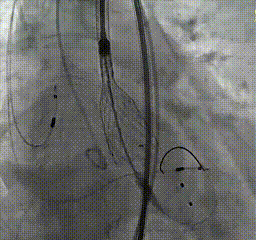

根部造影,导管测压70mmHg

球囊预扩,无腰征,无漏,考虑常规sizing,选用29mm THV

瓣膜在瓣环下精准定位,稳定释放

瓣膜释放后结果

最后造影

即刻超声未见瓣周漏,主动脉瓣峰值流速1.5m/s,平均压差4mmHg

最后造影亦未见反流,患者情况良好,手术顺利完成。